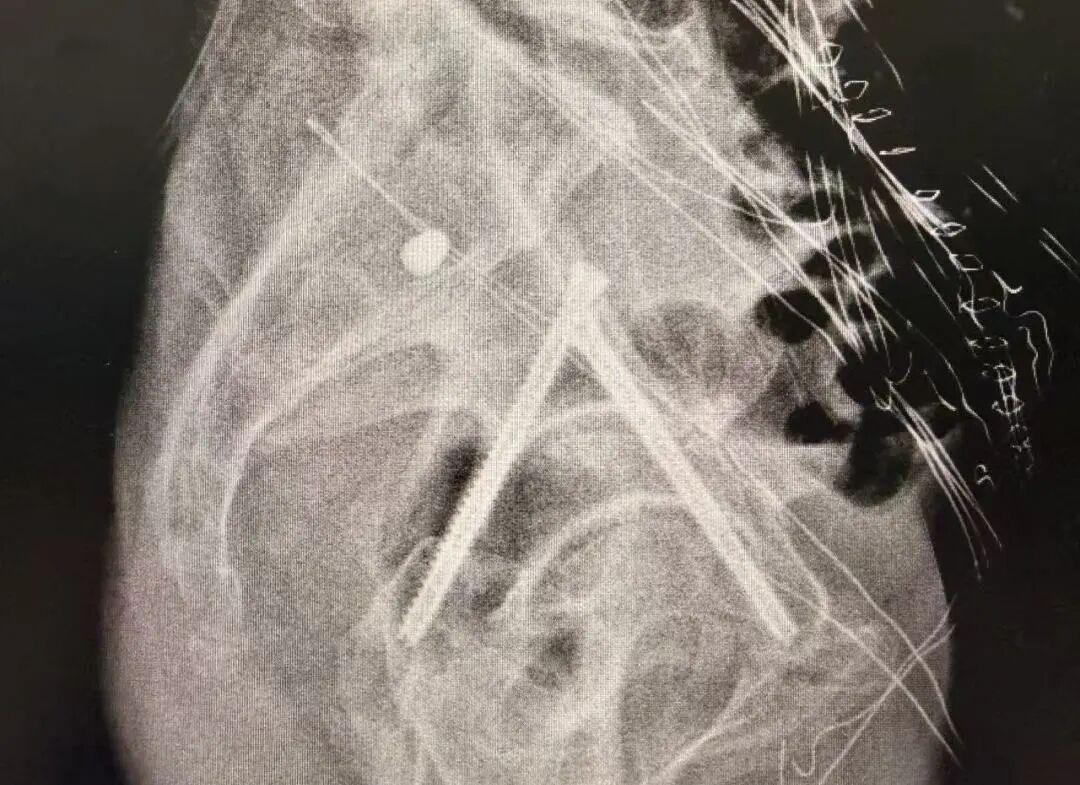

术中

机械臂按预设路径自动执行复位操作,精度高达毫米级,医生仅需通过几个微小切口置入内固定螺钉。

术后

术后患者恢复迅速,第二天已能下床站立。整个过程真正做到了“快、准、稳”,极大提升了手术安全性与疗效可控性。